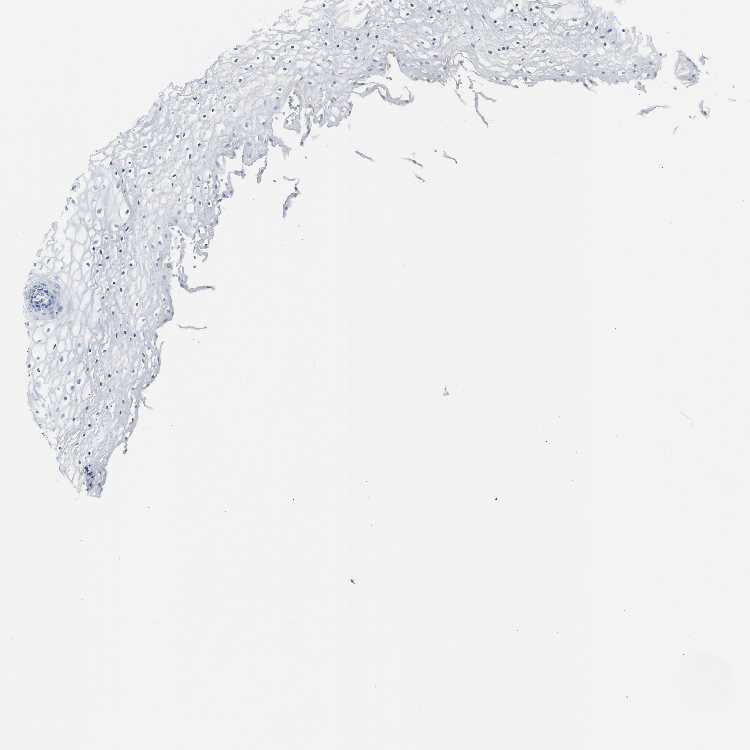

TISSUE PRIMARY DATA VAGINA Show tissue menu

VAGINA - Antibody stainingi

Antibody staining in the annotated cell types in the current human tissue is reported as not detected, low, medium, or high, based on conventional immunohistochemistry profiling in selected tissues. This score is based on the combination of the staining intensity and fraction of stained cells.

Each image is clickable and will lead to virtual microscopy that enables deeper exploration of all samples and also displays staining intensity scores, fraction scores and subcellular localization as well as patient and tissue information for each sample.

Antibody HPA036393Antibody HPA064556Antibody CAB007789

Squamous epithelial cells LowNot detectedNot detected